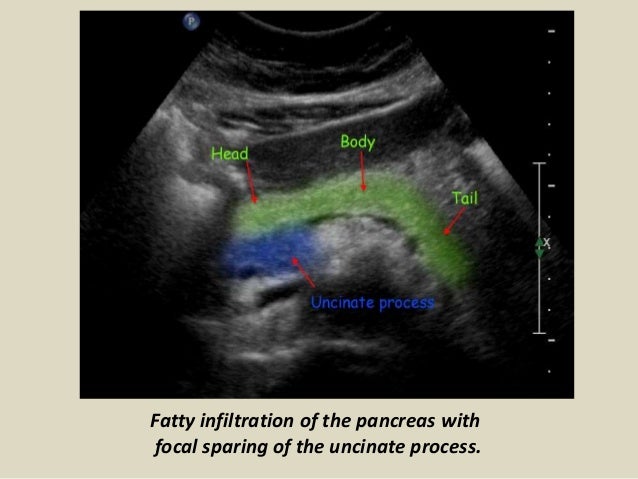

50+ Abdominal Vascular Anatomy Ultrasound. Introduction to sonographic abdominal anatomy. Abdominal ultrasonography (also called abdominal ultrasound imaging or abdominal sonography) is a form of medical ultrasonography (medical application of ultrasound technology) to visualise abdominal anatomical structures.

I will share with you key anatomical landmarks that once you recognize…will make. It is relatively quick, relatively inexpensive, can be correlated quickly with the patient's signs and symptoms, and, most importantly, does not employ ionizing radiation. I'll be undergoing the procedure in about four hours.